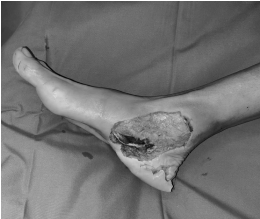

术前

很快,张允会、厉兵兵手术团队为患者进行了右足清创+岛状皮瓣修复术。右足跟皮肤撕脱,脚掌内侧可见大小约15cm*8cm的皮肤缺损,伤口内渗血,皮缘不齐,污染重,伤口内可见肌腱、肌肉断端外露。手术团队对污染严重的伤口予以“地毯式”彻底、反复清创。在高倍显微镜下缝合修复断裂的趾长屈肌、胫后肌腱、踇长屈肌腱,胫神经,修复撕脱皮肤,整个过程保持手部平稳,耐心吻接,然后根据创面缺损的大小、形状设计皮瓣并划线标记,游离血管蒂长度满足受区要求、血供良好的皮瓣,移植到脚部的残损创面,在显微镜下细致吻合血管、神经后皮瓣色红润,手术顺利完成,患者术后安返病房。